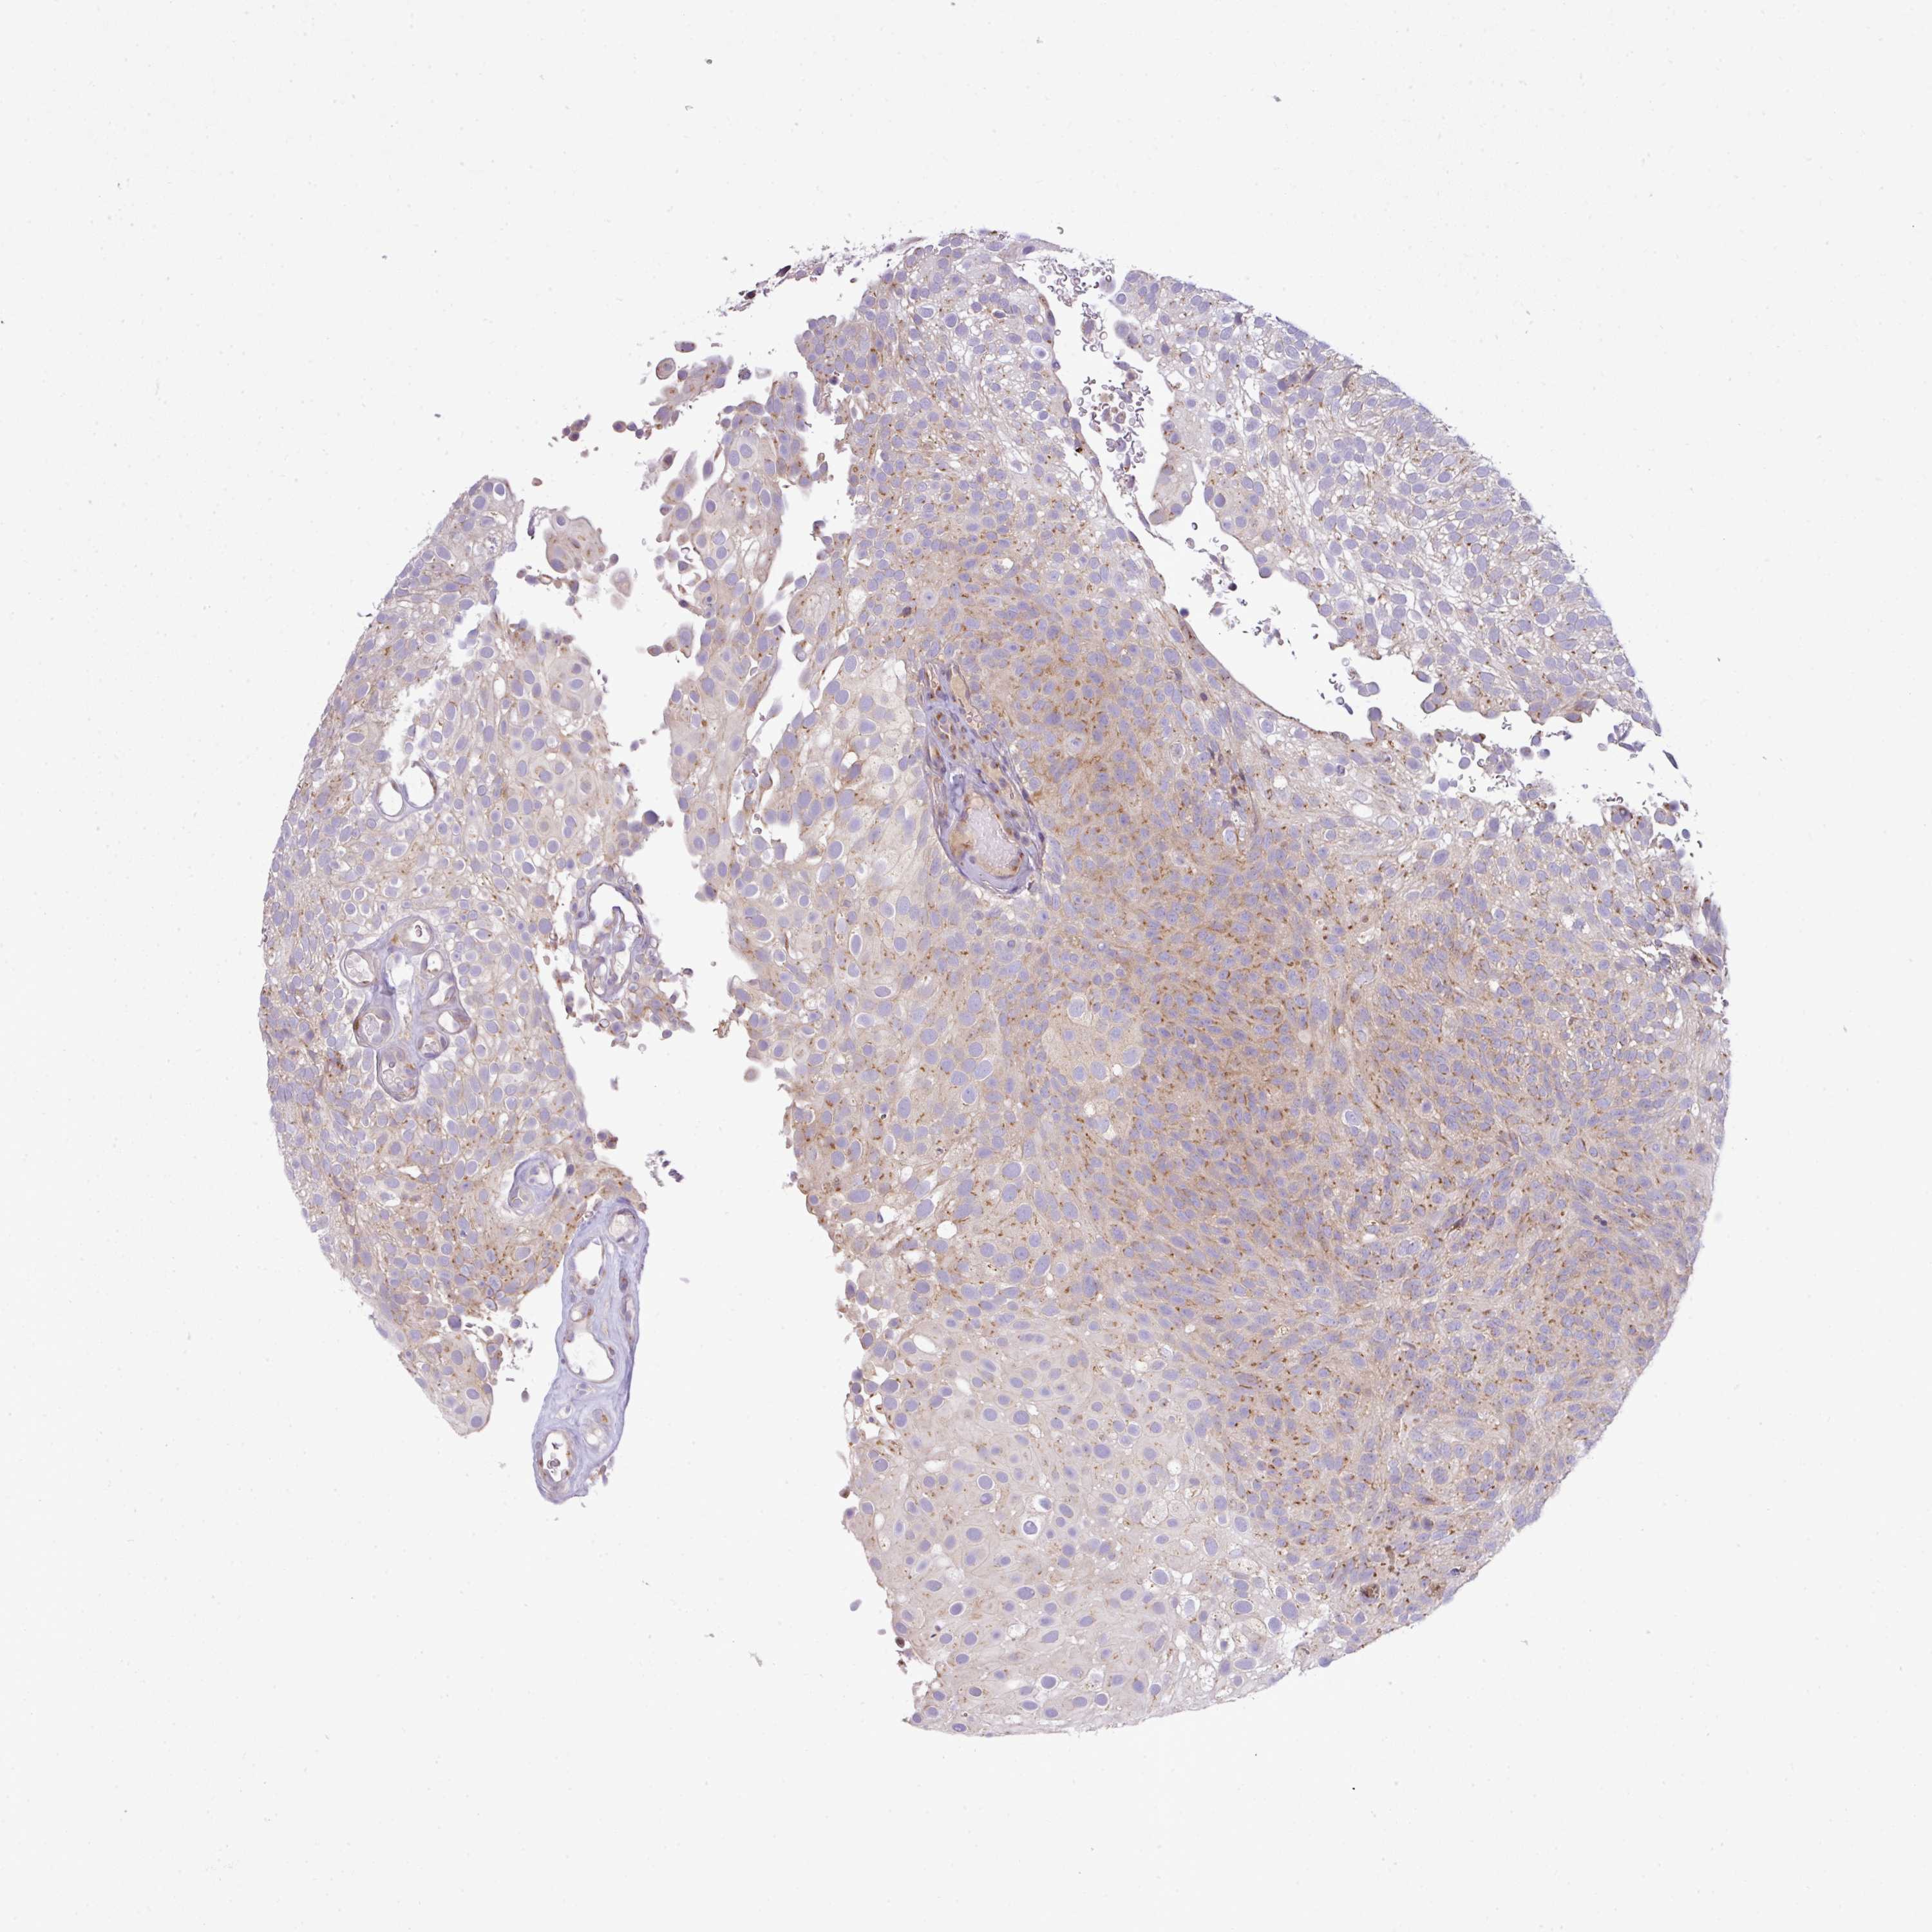

UROTHELIAL CANCER - Protein expressioni

A mouse-over function shows sample information and annotation data. Click on an image to view it in a full screen mode. Samples can be filtered based on level of antibody staining by selecting one or several of the following categories: high, medium, low and not detected. The assay and annotation is described here.

Note that samples used for immunohistochemistry by the Human Protein Atlas do not correspond to samples in the TCGA dataset.

Antibody stainingi

Antibody staining in the annotated cell types in the current human tissue is reported as not detected, low, medium, or high, based on conventional immunohistochemistry profiling in selected tissues. This score is based on the combination of the staining intensity and fraction of stained cells.

Each image is clickable and will lead to virtual microscopy that enables deeper exploration of all samples and also displays staining intensity scores, fraction scores and subcellular localization as well as patient and tissue information for each sample.

Antibody HPA054108

Staining

High

Medium

Low

Not detected

Intensity

Strong

Moderate

Weak

Negative

Quantity

>75%

75%-25%

<25%

None

Location

Urothelial carcinoma, High grade

Urothelial carcinoma, NOS

Urothelial carcinoma, Low grade